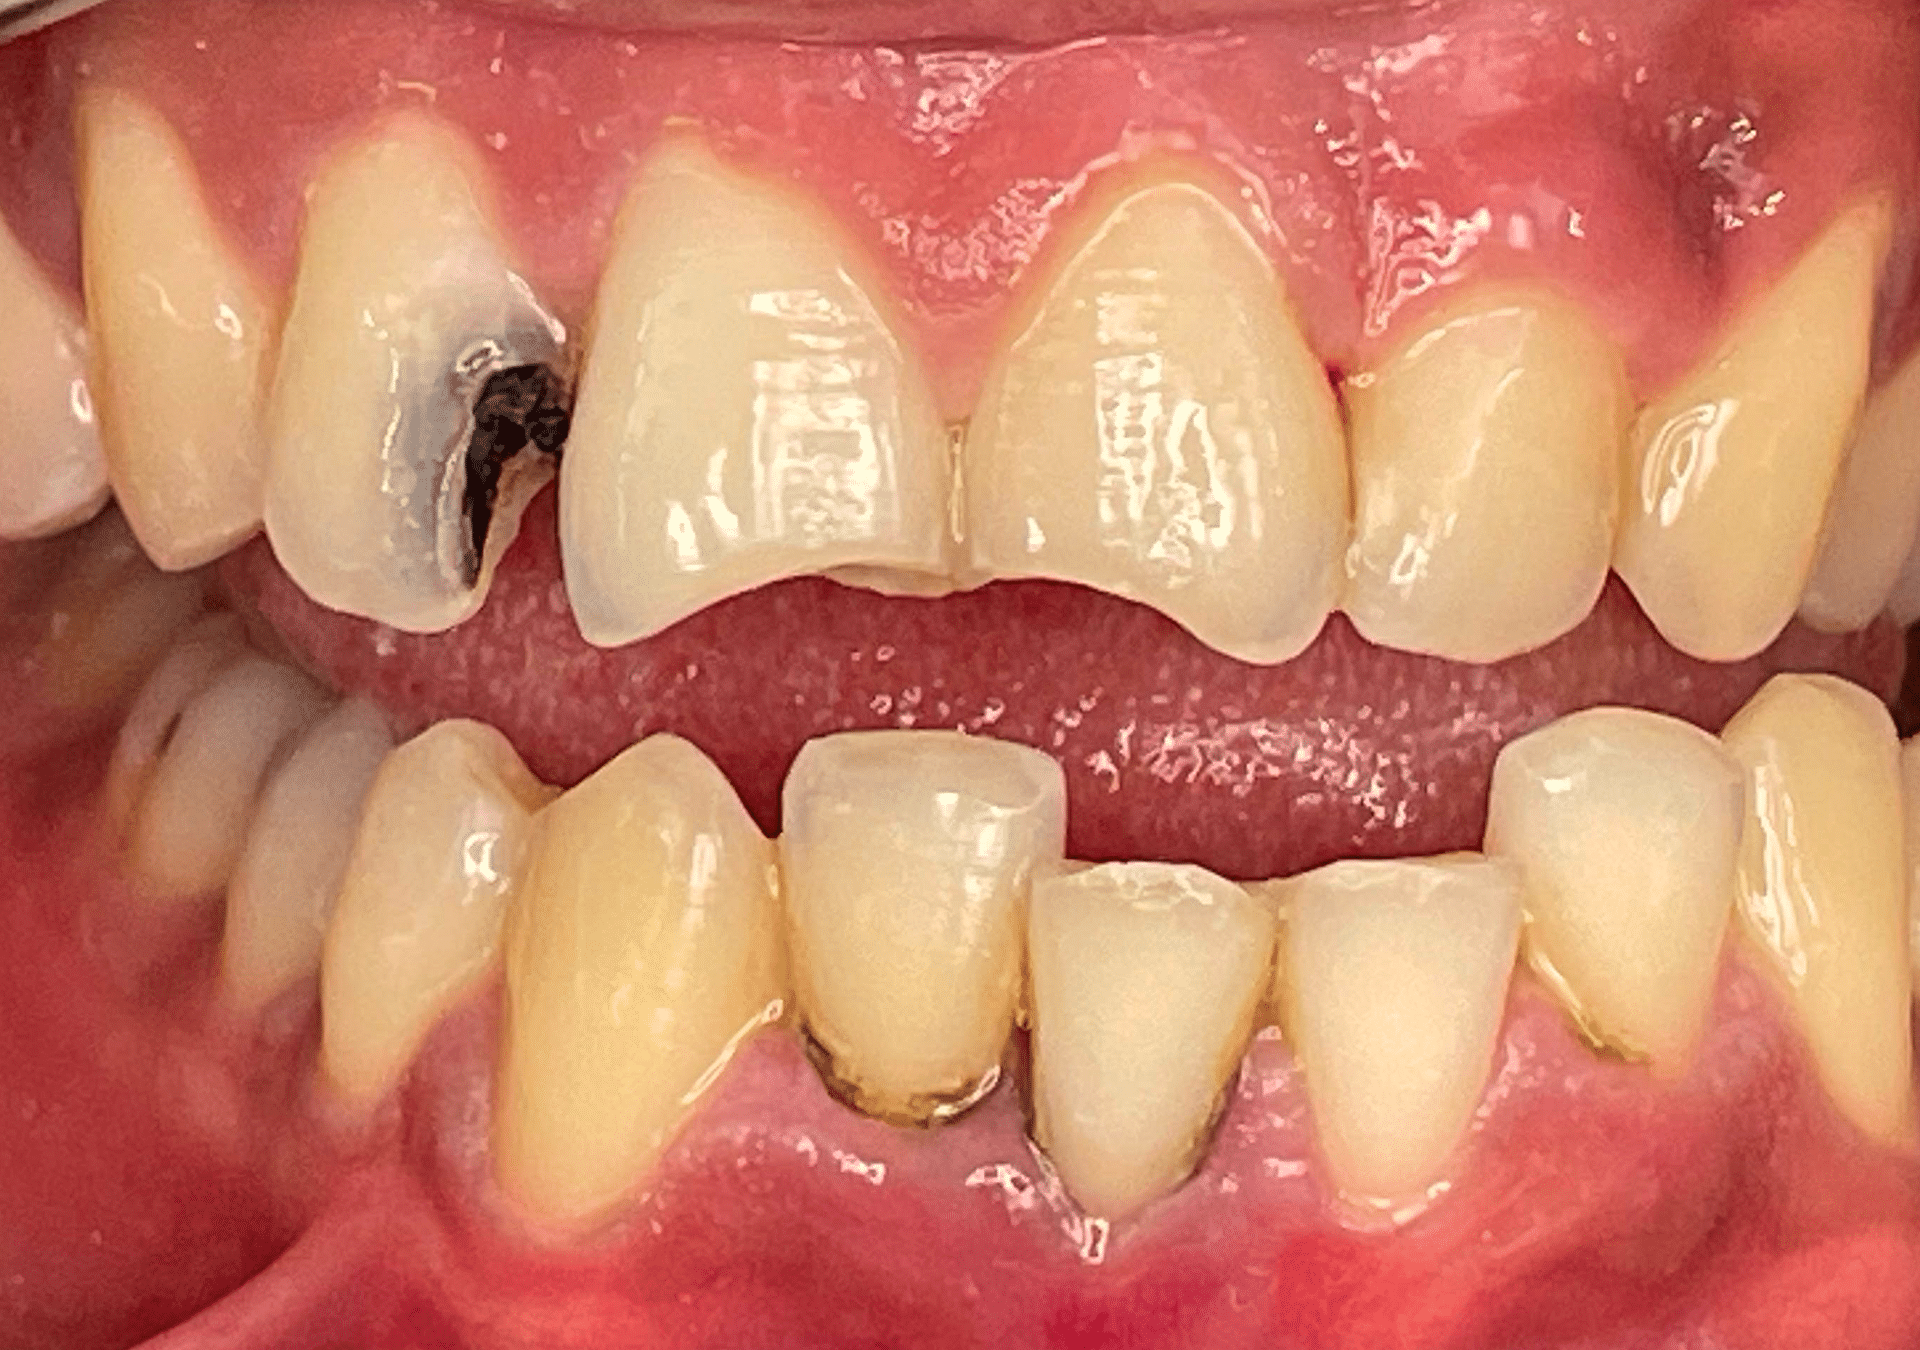

Rehabilitación con cerámica feldespática de paciente con amelogénesis imperfecta (esmalte defectuoso), eliminación de tinciones y protección superficies.